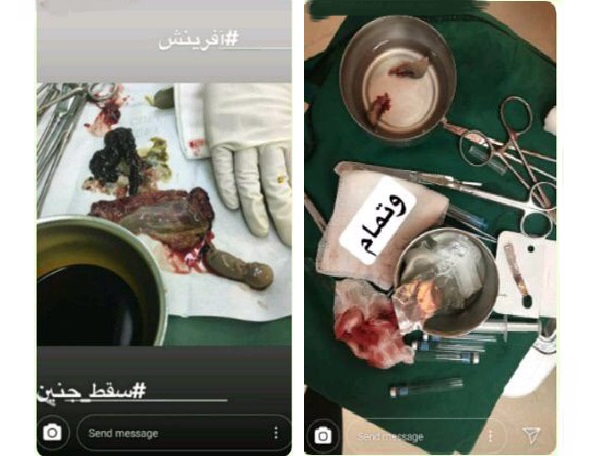

تبلیغ در فضای مجازی موضوعی جدید نیست، اما به تازگی انتشار تصاویری نامتعارف از انجام عمل جراحی یا نحوه مصرف دارو سقط جنین به معضلی حاد تبدیل شده است.[

, شبکه اطلاع رسانی راه دانا,اعمالی غیر قانونی که روزگاری عدهای از صحبت درباره آنها شرم داشتند و حتی گاهی آن را کتمان میکردند، امروز به افتخارات و محل درآمد برخی تبدیل شده است؛ تصاویر خط قرمزی که امروزه بدون فیلتر و تنها برای تبلیغات برخی پزشکان در صفحات مجازی منتشر میشوند.

خداکرمی درباره تصاویر منتشر شده از تبلیغات نامتعارف یک متخصص مامایی، اظهار کرد: اغلب تصاویر منتشر شده از این تبلیغات غیر معمول به یکی از متخصصان این حوزه در استان مازندران مربوط بوده، این پزشک با استفاده از فضای مجازی و تنها برای تبلیغات اقدام به انتشار و پخش تصاویر نامتعارفی از این حوزه میکرده است.

اعمالی غیر قانونی که روزگاری عدهای از صحبت درباره آنها شرم داشتند و حتی گاهی آن را کتمان میکردند، امروز به افتخارات و محل درآمد برخی تبدیل شده است؛ تصاویر خط قرمزی که امروزه بدون فیلتر و تنها برای تبلیغات برخی پزشکان در صفحات مجازی منتشر میشوند.

, خداکرمی درباره تصاویر منتشر شده از تبلیغات نامتعارف یک متخصص مامایی، اظهار کرد: اغلب تصاویر منتشر شده از این تبلیغات غیر معمول به یکی از متخصصان این حوزه در استان مازندران مربوط بوده، این پزشک با استفاده از فضای مجازی و تنها برای تبلیغات اقدام به انتشار و پخش تصاویر نامتعارفی از این حوزه میکرده است.